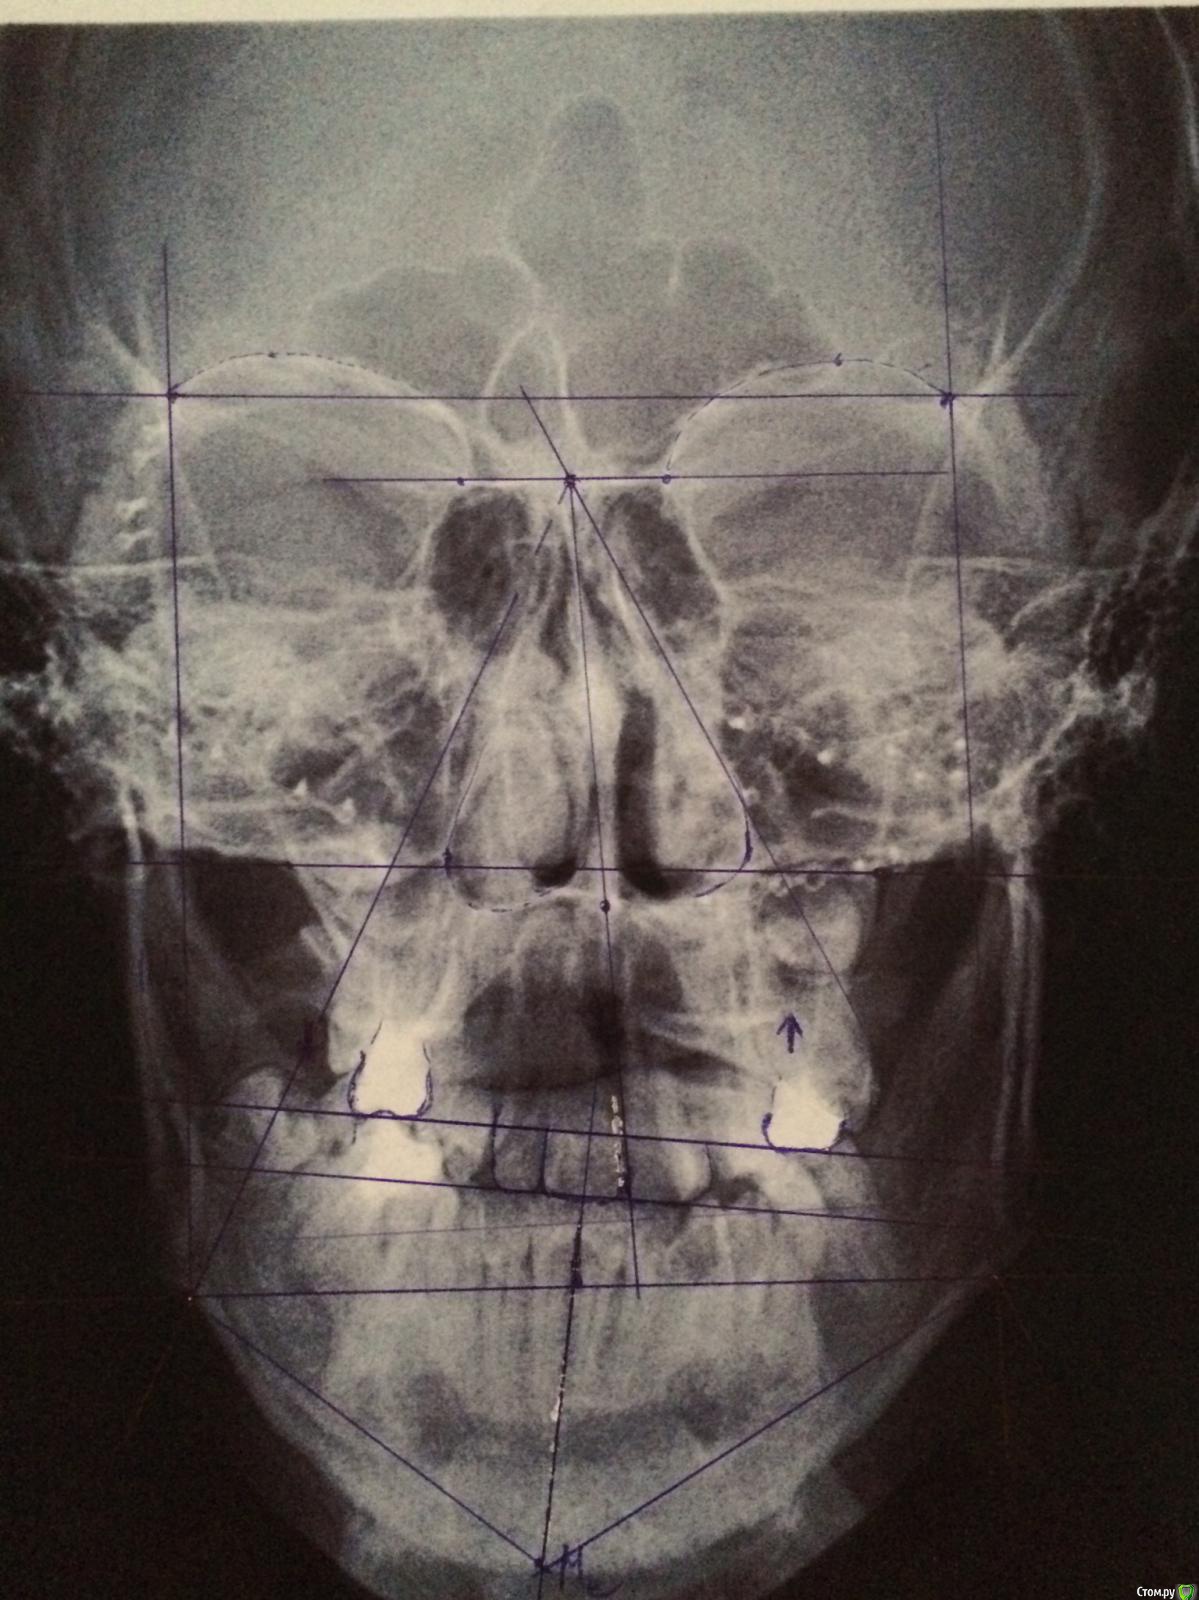

Maverick Опубликовано 29 августа, 2015 Поделиться Опубликовано 29 августа, 2015 (изменено) Доброго времени суток. В клинику обратился пациент. В детстве была травма лицевого скелета в возрасте 13 лет. Упали футбольные ворота. Было проведено хирургическое вмешательство по ре позиционировнию костных отломков скуловых, орбитальных костей. Были даны рекомендации вернуться через год на повторный осмотр, но так получилось, что этого сделано не было. Что имеем по факту. При осмотре лица заметно девиация нижней челюсти в левую сторону, не критичную,обычный человек не обратит внимание, но бросающуюся в глаза если смотреть в кресле. Из данных трг анализа , скелетный 3 класс, wits -6(не очень критично ), увеличенный размер нижней челюсти по сравнению с нормой, ANB -1,5 , ретроположение всего лицевого скелета. Строго вертикальный тип роста, долихофациальный. Sn-mp 41. В полости рта все куда хуже, суженная верхняя челюсть, нехватка ширины порядка 7 мм в области премоляров и 5 мм в области моляров, благодаря чему мы получаем перекретный прикус, первый класс по молярам и клыкам слева и третий справа, вторичная адентия на нижней челюсти 46. Смещение центральной линии влево на целый резец. И еще приятный бонус это кант окклюзионной плоскости, во втором квадранте вверх в первом вниз. Интересно мнение коллег. Изменено 29 августа, 2015 пользователем Maverick Ссылка на комментарий

Maverick Опубликовано 29 августа, 2015 Автор Поделиться Опубликовано 29 августа, 2015 Оптг у пациентов к сожалению.17 лет на данный момент. 45 зуб так интересно сместился что и меня ввел в небольшой ступор. 46 был удален давно. Фоток нет к сожалению пока нет, профиль прямой, в фас видно увеличение нижней трети лица. Разница в длине ветвей присутствует слева длиннее на 3 мм. Девяток нет ) это все качество снимков. Пациент впринципе не радикально хирургический. Можно провести достойную компенсацию. В мыслях была микроимплантация для ротации плоскости и конечно расширение верхнего зубного ряда что само собой разумеется., думаю тогда нижняя челюсть заняла бы оптимальную позицию, а не вынужденную ,как сейчас и смещение не было бы так выражено. Вся информация что имеется на данный момент представлена. Ссылка на комментарий